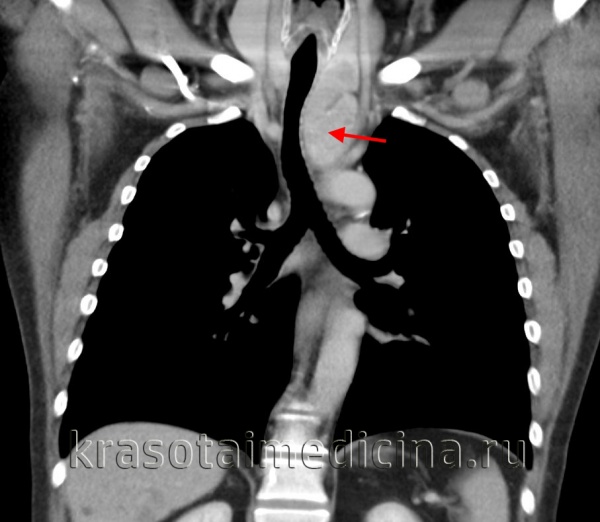

КТ ОГК. Массивное объемное образование верхнего средостения с объемным воздействием на трахею, исходящее из щитовидной железы.

- Рентгеновская диагностика. Комплексное рентгенологическое обследование в большинстве случаев позволяет четко определить локализацию, форму и размеры опухоли средостения и распространенность процесса. Обязательными исследованиями при подозрении на опухоль средостения являются рентгеноскопия грудной клетки, полипозиционная рентгенография, рентгенография пищевода. Данные рентгенологического исследования уточняются с помощью КТ грудной клетки, МРТ или МСКТ легких.

Обязательный перечень рентгенологических исследований включает рентгенографию грудной клетки, рентгенографию пищевода с контрастированием, компьютерную томографию. В большинстве случаев проведенное обследование позволяет установить локализацию рака средостения и распространенность процесса, заинтересованность органов грудной полости (легких, диафрагмы, аорты, грудной стенки). Уточнить состояние мягких тканей в зоне новообразования, выявить метастазы опухоли в лимфоузлы и легкие помогает МРТ.